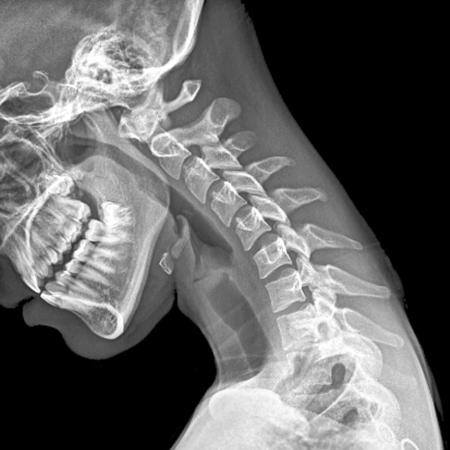

Problemas cervicales

Las cervicales están ligeramente curvadas hacia delante formando una lordosis y proporcionando gran flexibilidad y movilidad. El cuello soporta el peso de la cabeza y está contínuamente mandando impulsos nerviosos al cerebro: cada vez que movemos el cuerpo, la cabeza o los ojos también movemos unos grados los segmentos vertebrales cervicales. Esta coordinación fluida de